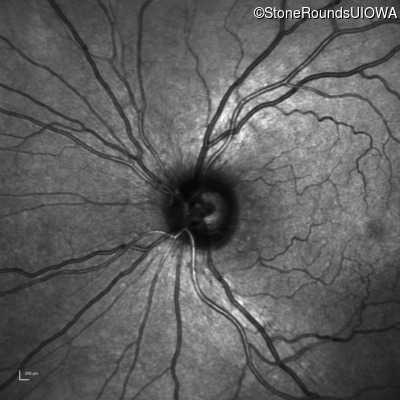

Infrared Fundus Photograph - Right - 20/400 sc

Exemplar